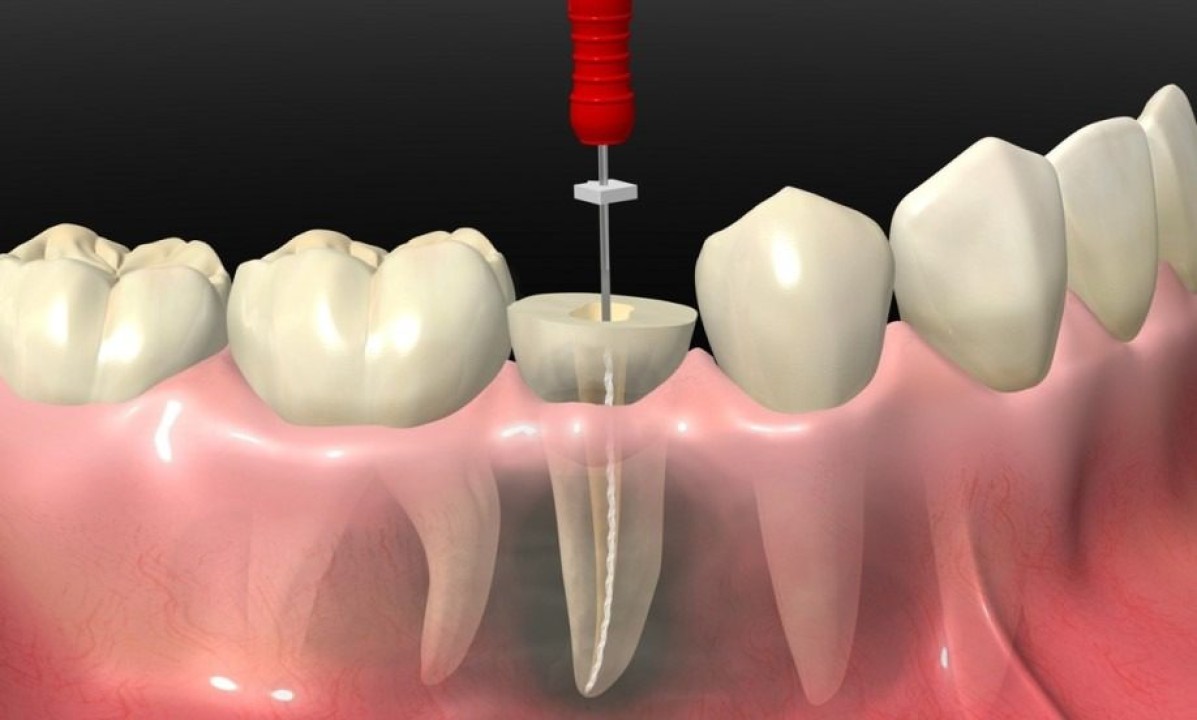

برای عصب کشی دندان دندانپزشک پس از تزریق بی حسی و با استفاده از مته، سوراخی در بالا یا پشت دندان ایجاد کرده و به سیستم ریشه و محفظه پالپ دسترسی پیدا می کند. پس از آن بافت های عصبی مرده را خارج و پالپ را از داخل پاک می کند.

از آنجایی که کانال های ریشه اغلب منحنی و نازک هستند، دندانپزشک به مدتی زمان نیاز دارد تا بتواند به تمام بافت های مرده دسترسی پیدا کرده و آنها را خارج کند. در نتیجه عصب کشی دندان به خصوص برای دندان هایی با چندین ریشه، حتی چندین ساعت طول بکشد.